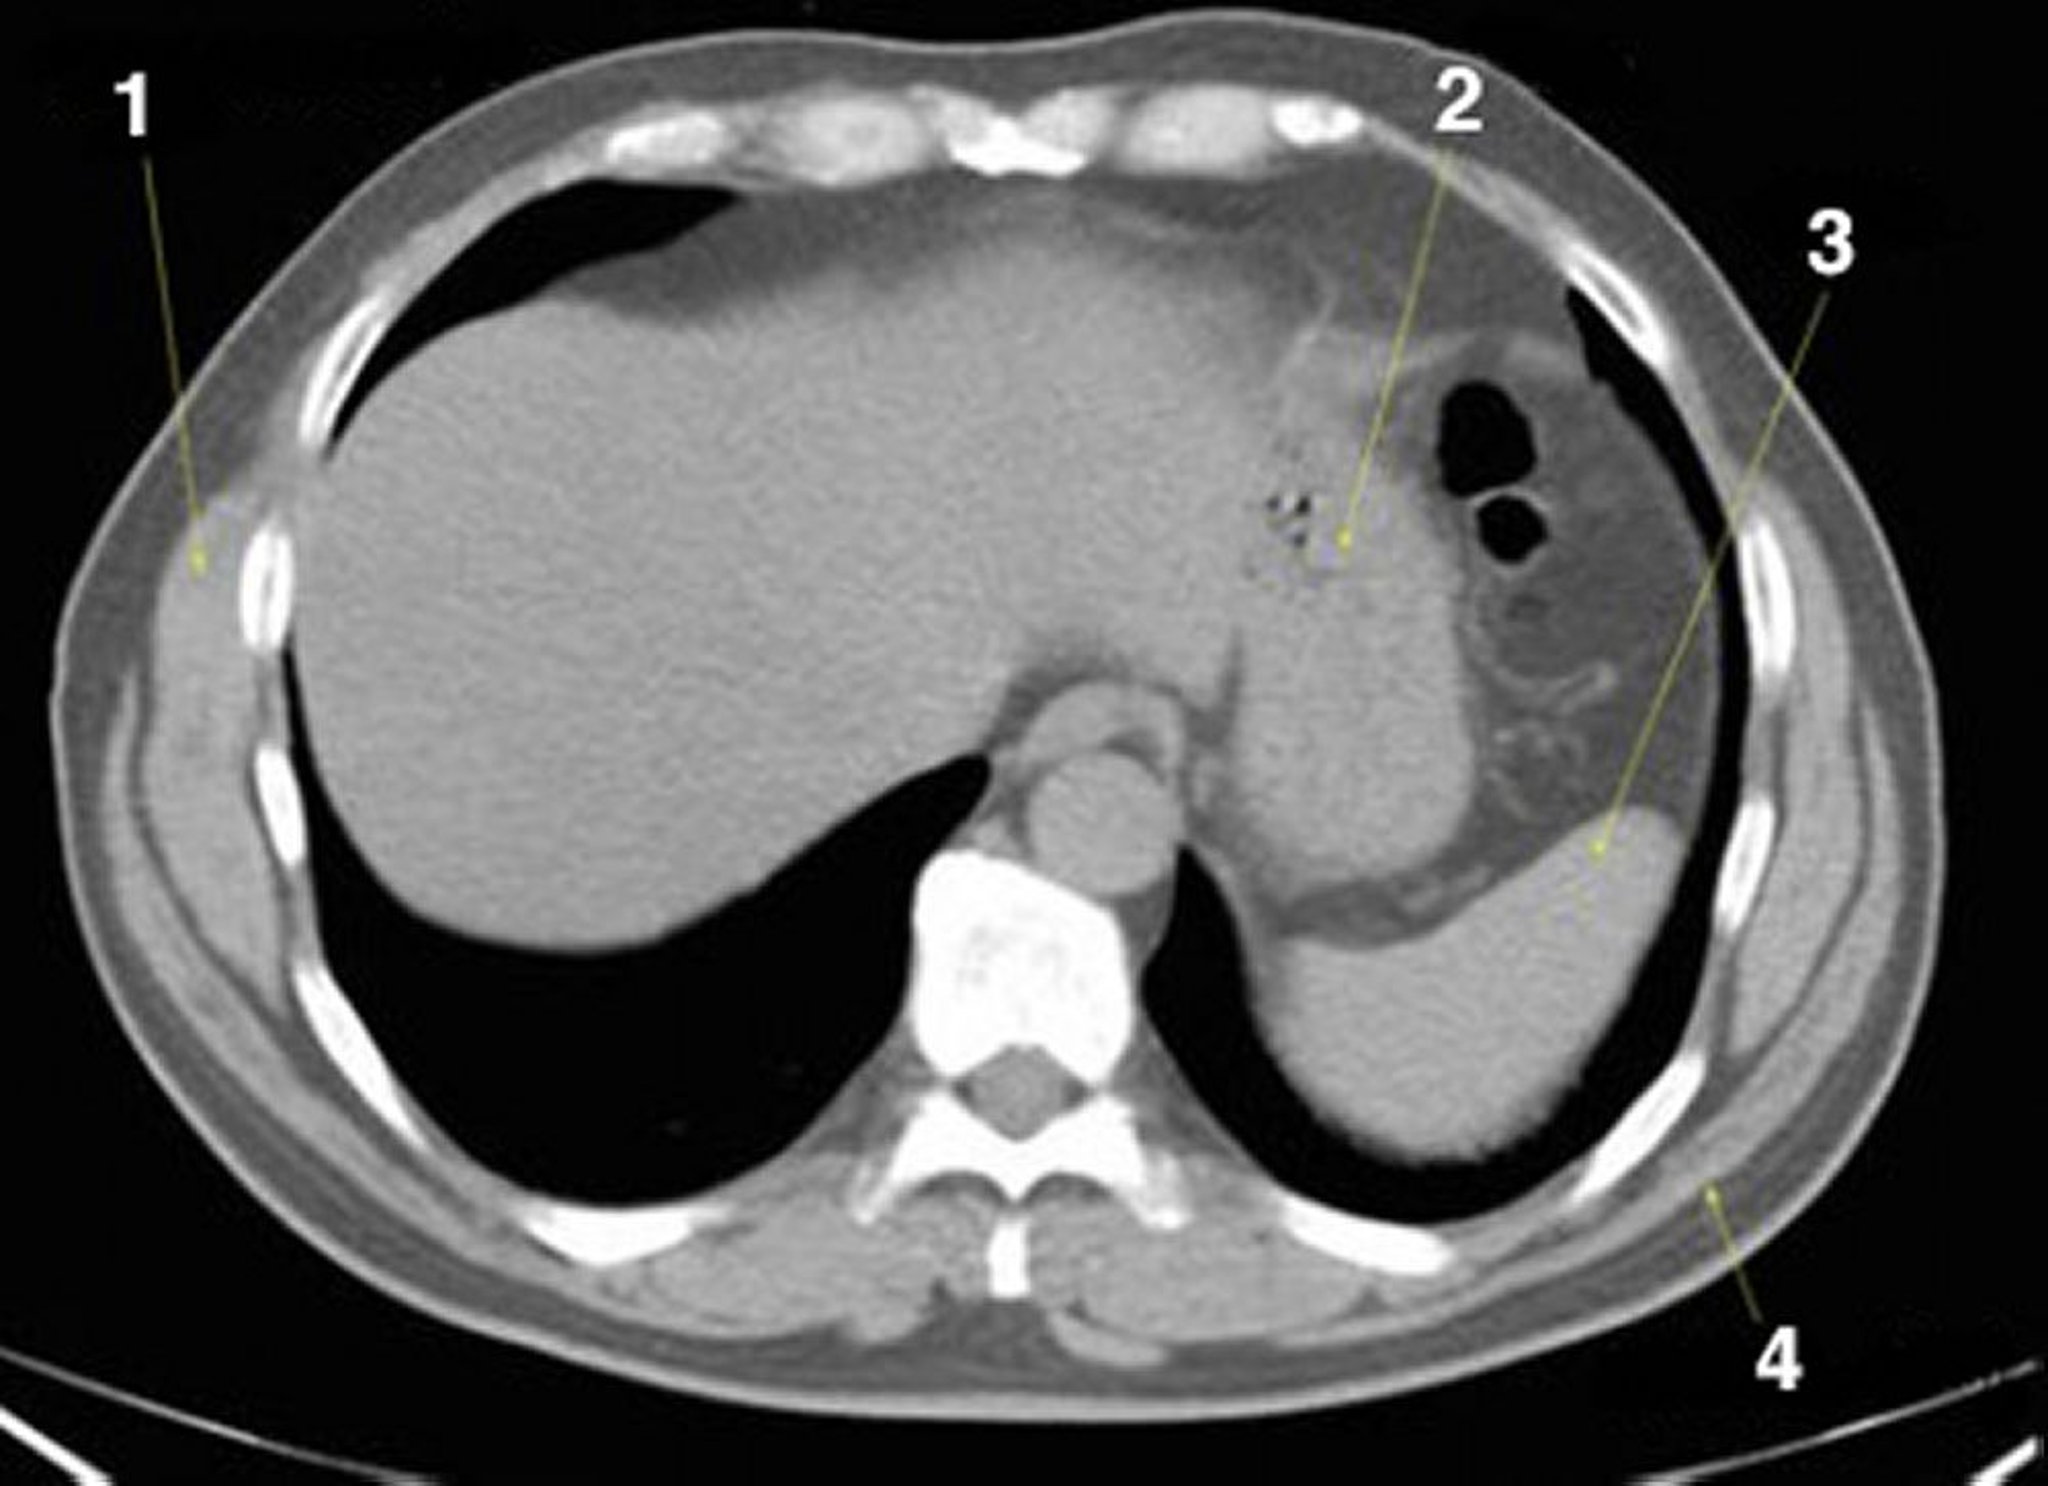

Noncontrast CT Scan of the Abdomen and Pelvis Showing Normal Anatomy (Slide 2)

1 = serratus anterior; 2 = stomach; 3 = spleen; 4 = latissimus dorsi.